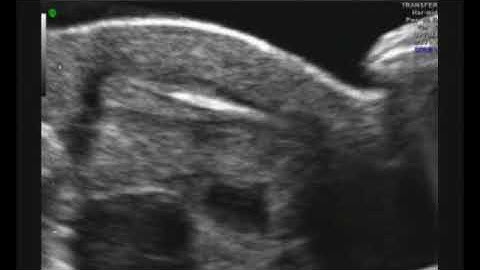

Embryo Transfer